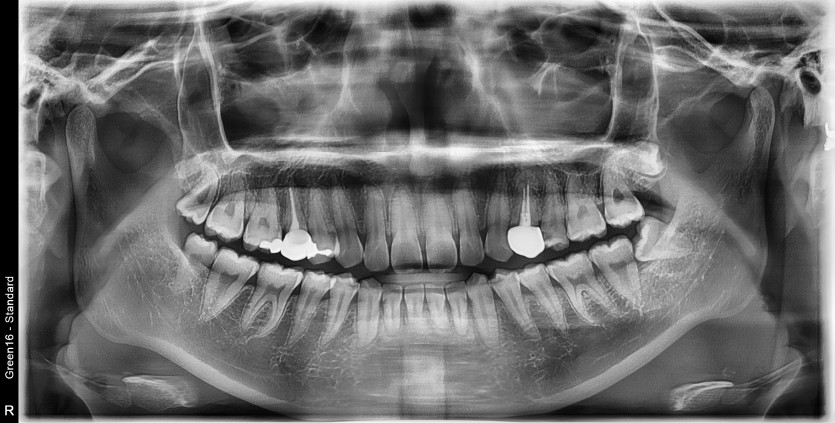

#38 사랑니 발치

구강 외과 전문의가 당일 발치했습니다.